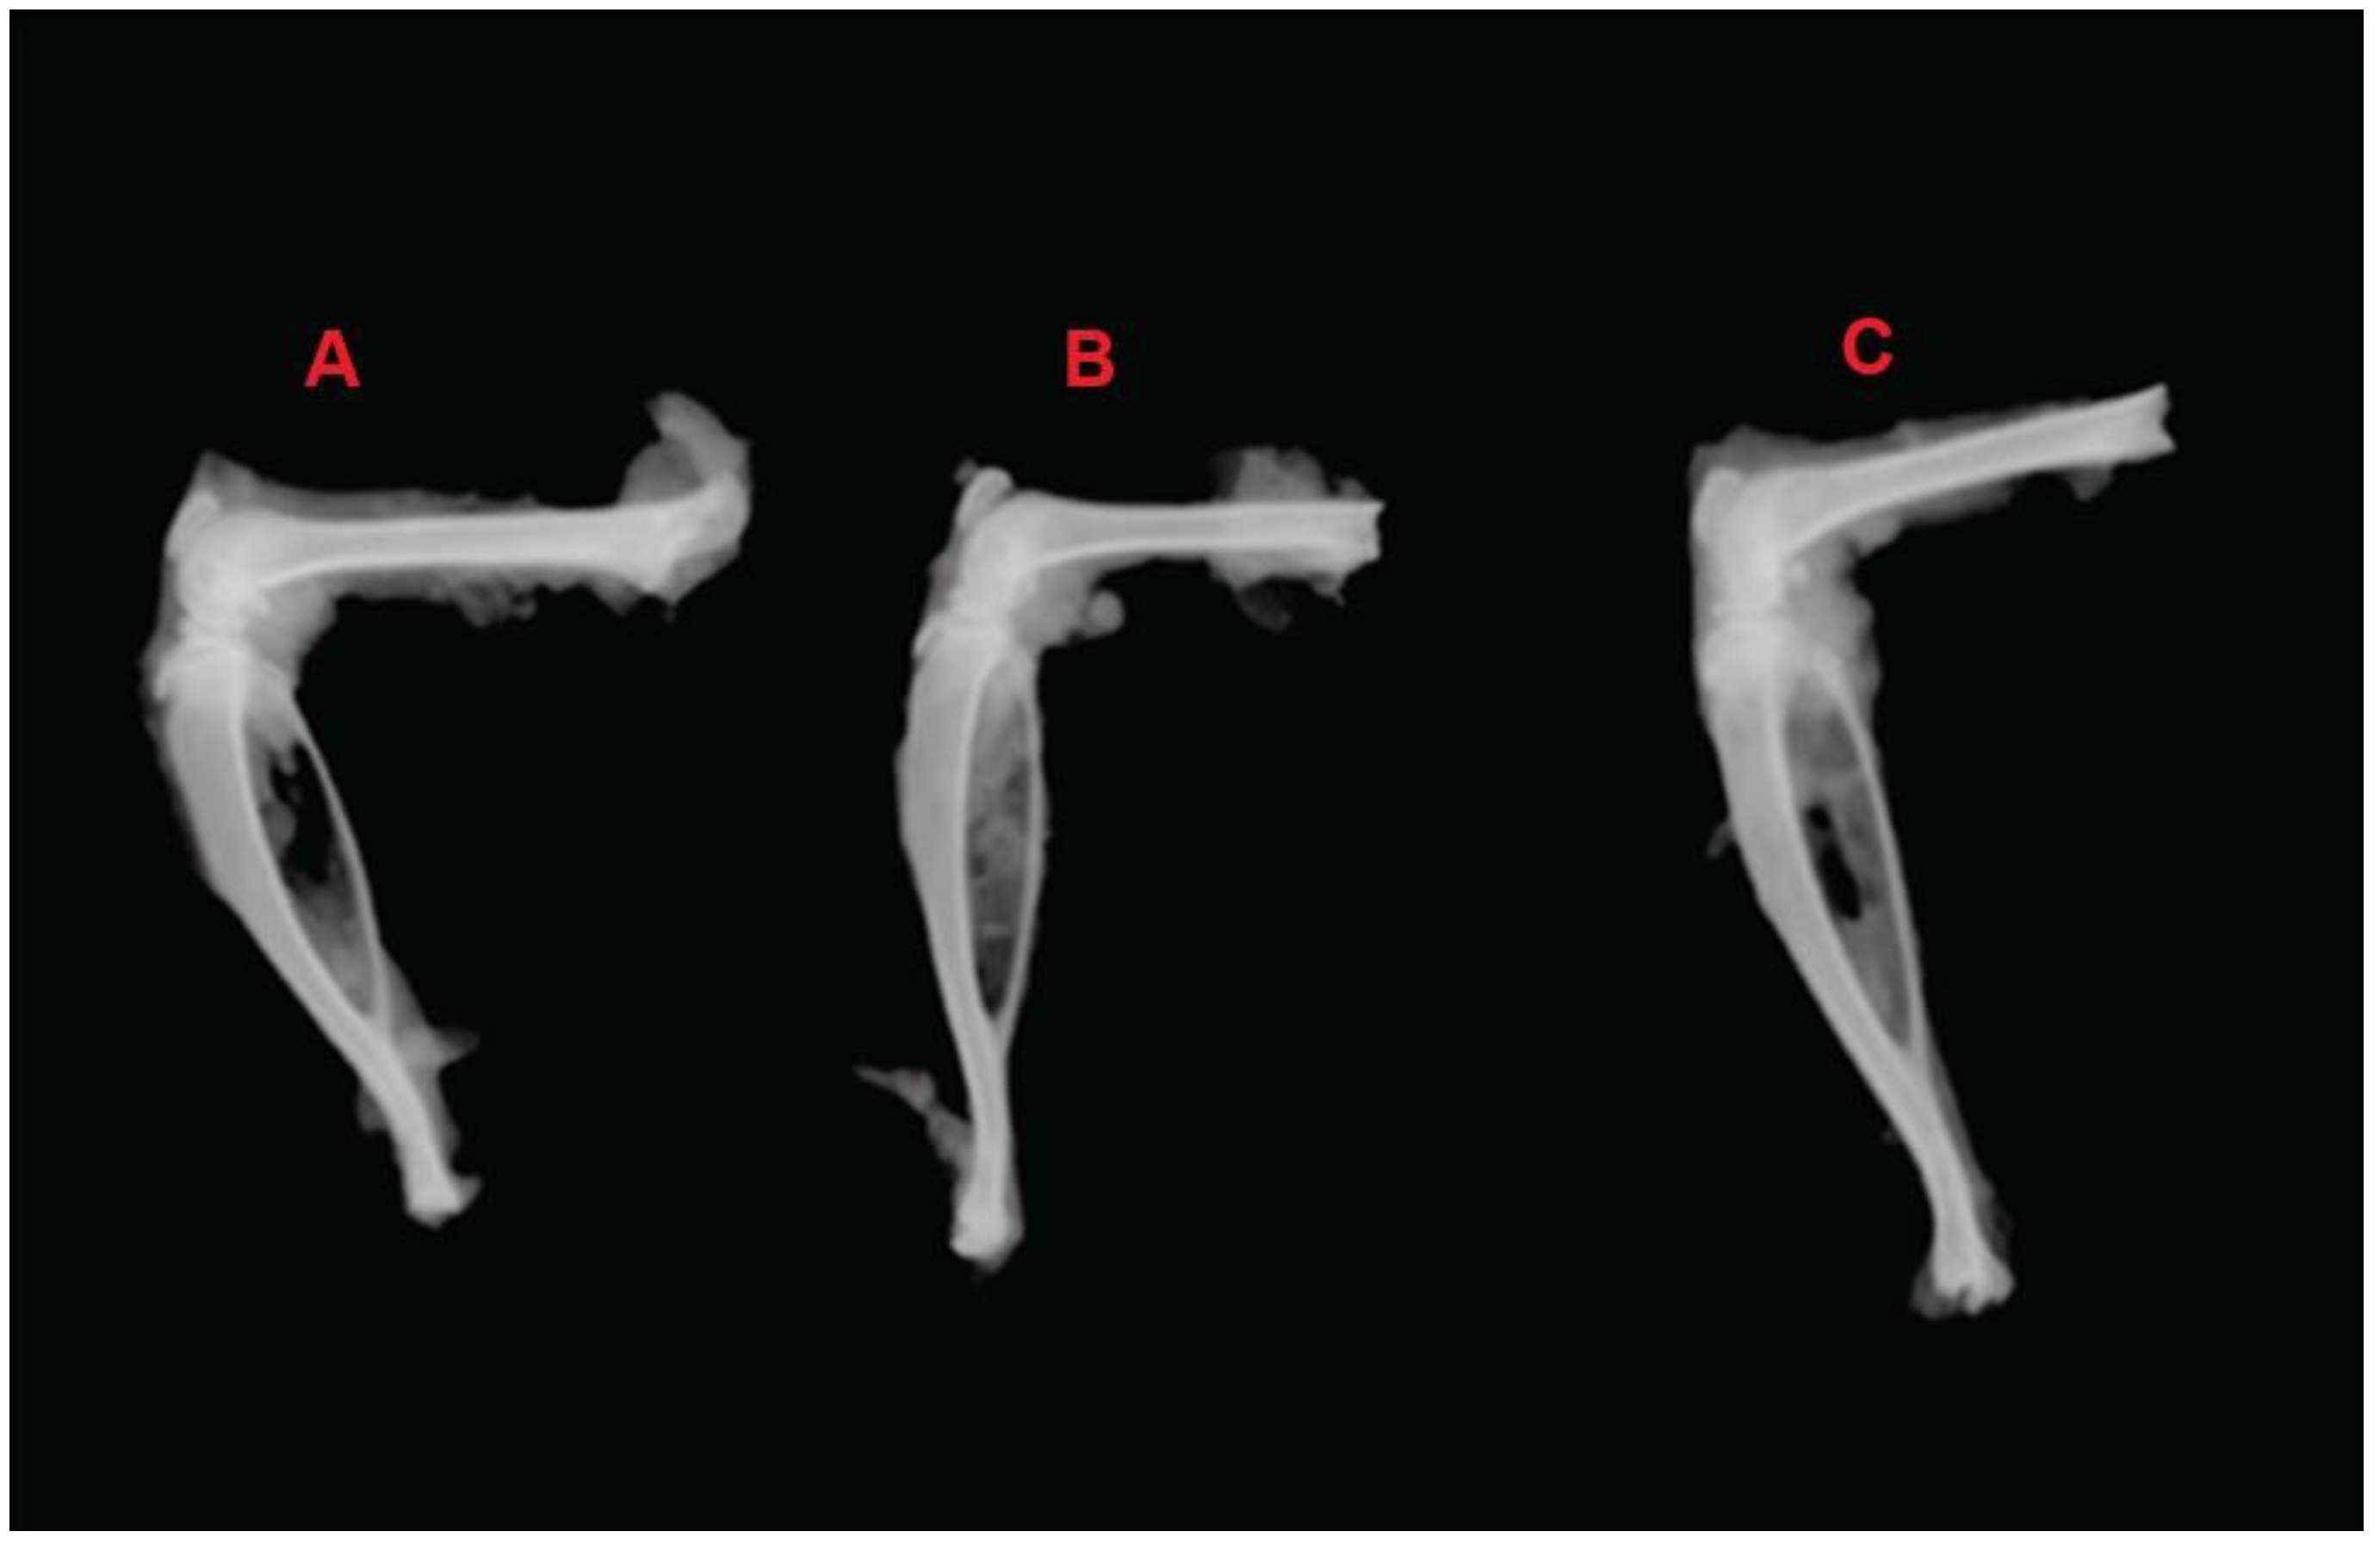

2.8. In Vivo Anti-Arthritic Activity of Nanoemulsion

3.2.9. In Vivo Anti-Arthritic Activity

- Cui, X.; Wang, R.; Bian, P.; Wu, Q.; Seshadri, V.D.D.; Liu, L. Evaluation of antiarthritic activity of nimbolide against Freund’s adjuvant induced arthritis in rats. Artif. Cells Nanomed. Biotechnol. 2019, 47, 3391–3398. [Google Scholar]

- Singh, V.S.; Dhawale, S.C.; Shakeel, F.; Faiyazuddin, M.; Alshehri, S. Antiarthritic Potential of Calotropis procera Leaf Fractions in FCA-Induced Arthritic Rats: Involvement of Cellular Inflammatory Mediators and Other Biomarkers. Agriculture 2021, 11, 68. [Google Scholar] [CrossRef]